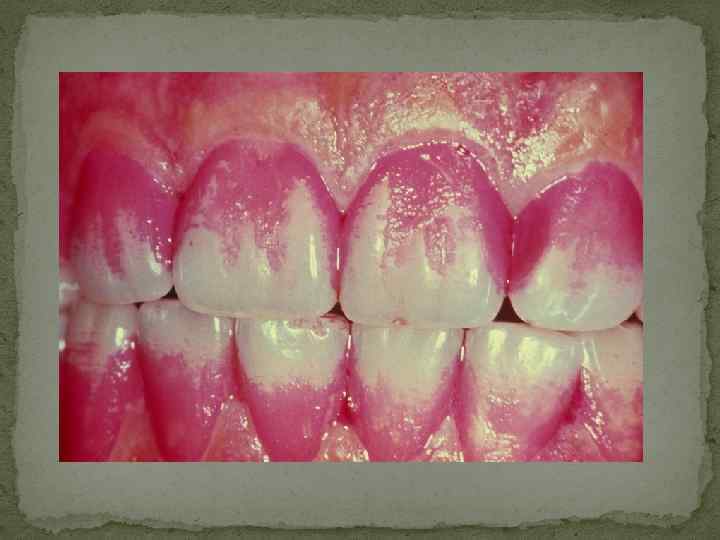

Клинические методы